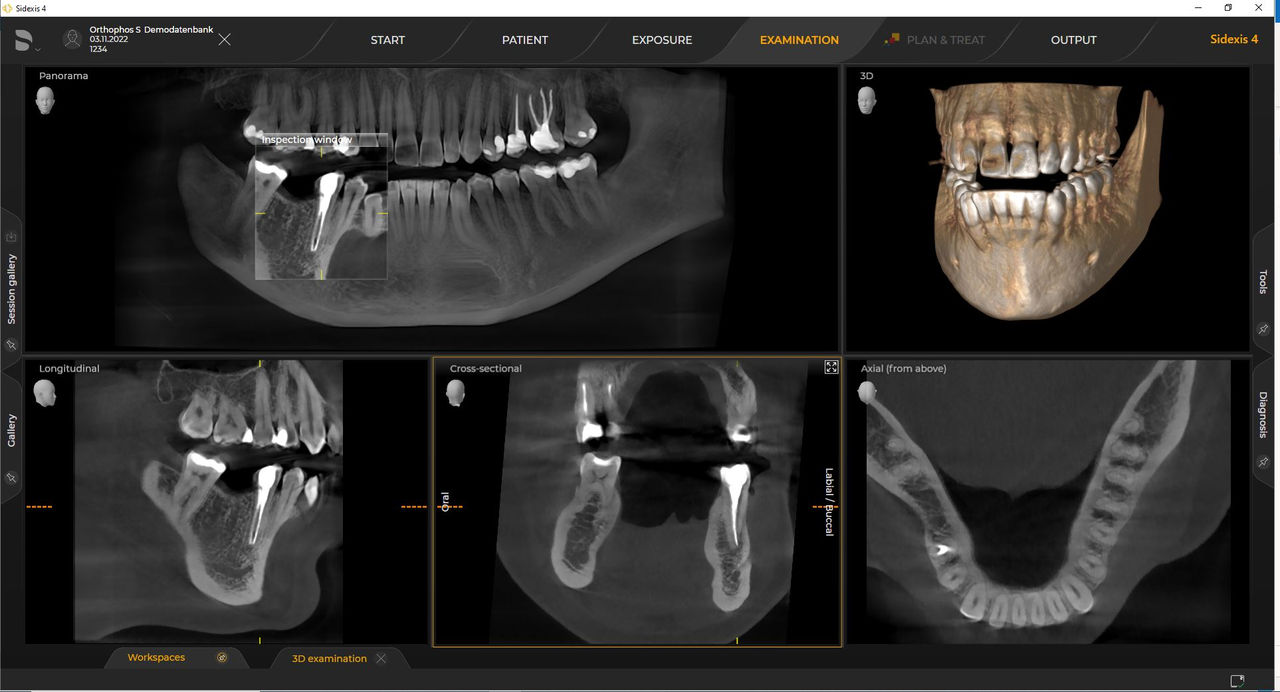

Las unidades de radiología de Dentsply Sirona funcionan exclusivamente con Sidexis 4. Sin embargo, la migración de datos de Sidexis XG a Sidexis 4 es muy fácil. Sidexis 4 permite una experiencia digital completa con las últimas herramientas

Con el modo de dosis baja inteligente 3D, obtiene imágenes 3D en el rango de dosis de una imagen radiológica 2D. En el modo HD (hasta 1400), las imágenes individuales se obtienen durante una única rotación y se convierten en un volumen 3D con hasta 80 μm para imágenes de bajo ruido en alta resolución.